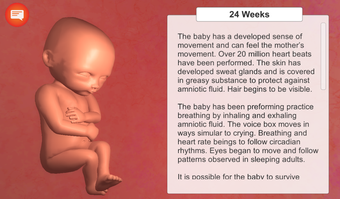

La aplicación está dividida en varias secciones, y cada sección contiene una descripción detallada y varios modelos 3D de alta calidad de las etapas clave del desarrollo del embarazo. Es muy fácil navegar por las secciones, y se puede cambiar entre ellas para ver diferentes etapas.